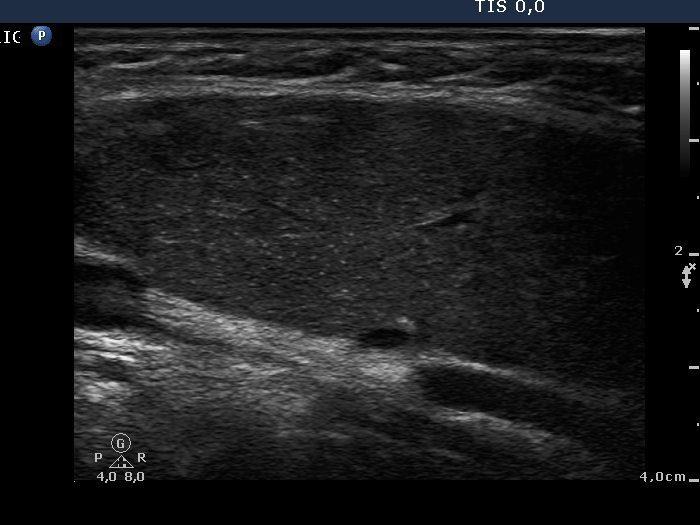

Ultrasonography: A hypoechogenic, inhomogeneous thyroid was found with increased vascularization.